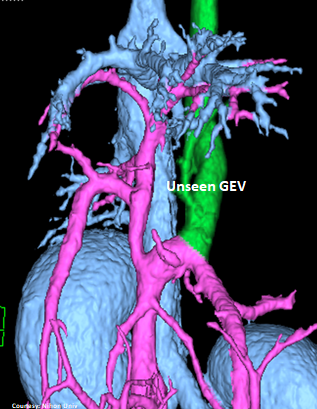

POST-HEPATIC ENTRANCE

(Azygos Vein entrance)

Does the GASTROEPIPLOIC VEIN (GEV) contribute blood to the shunt?

WEISSE 2022

slide71

“LGA +RGV -GSV”

Left Gastric – Azygos Vein Shunt with Right Gastric Vein contribution and absent Gastrosplenic Vein (does not enter PV)

Courtesy: Nihon Univ